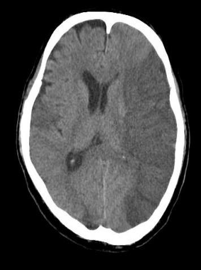

Infarction appear hypodense on CT

Cerebral infarct in the left cerebral hemisphere

In some cases infarct is not clear initially on CT but after 48 to 72 hours itΒ becomes more apparent